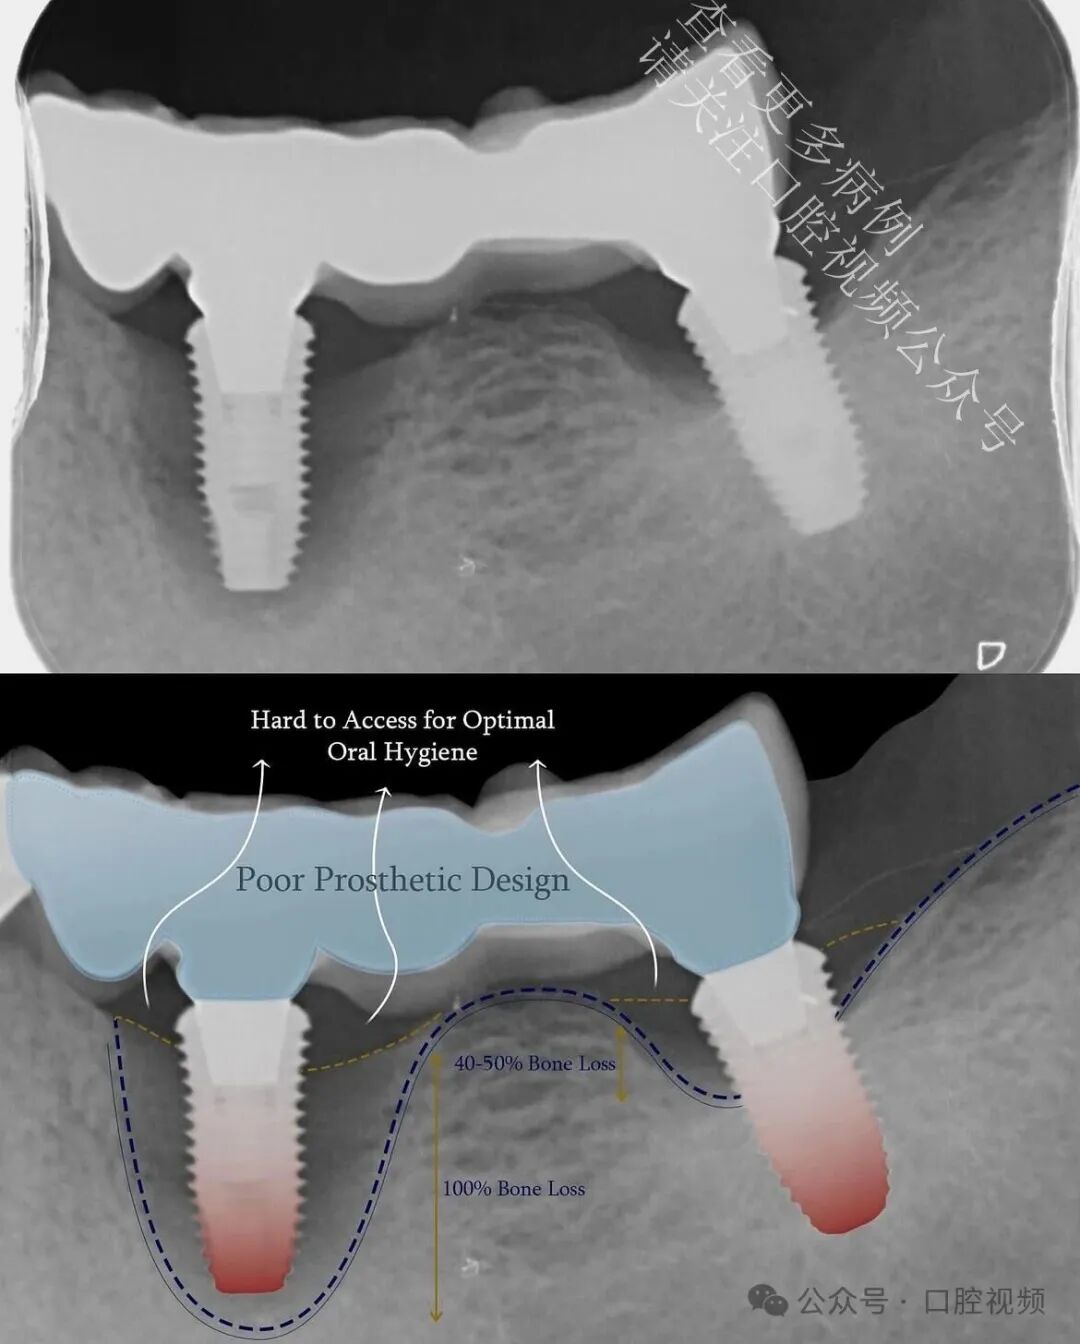

在对远中种植体周围实施非手术牙周治疗以稳定软组织后,该种植体开始出现自然的骨增量。未进行任何植骨术,仅通过更健康的轮廓形态、炎症减轻以及为生物学修复留出空间,便实现了这一转变。观察到远中种植体周围骨量增加及组织健康状况改善后,我们决定予以保留。

远中种植体(LL7)开始出现自然的骨增量——此处并未进行任何植骨操作。仅仅是形成了更健康的软组织轮廓、炎症显著减轻,并为生物学自我修复创造了条件。最初,我计划拔除这颗已出现失败迹象的种植体,仅修复 LL5 和 LL6;但鉴于 LL7 周围骨量增加及组织健康状况明显改善,我们最终决定保留并修复该种植体。

这再次印证了一个理念:当我们停止对生物学的侵扰,转而尊重其内在规律时,生物学本身便展现出惊人的修复能力。